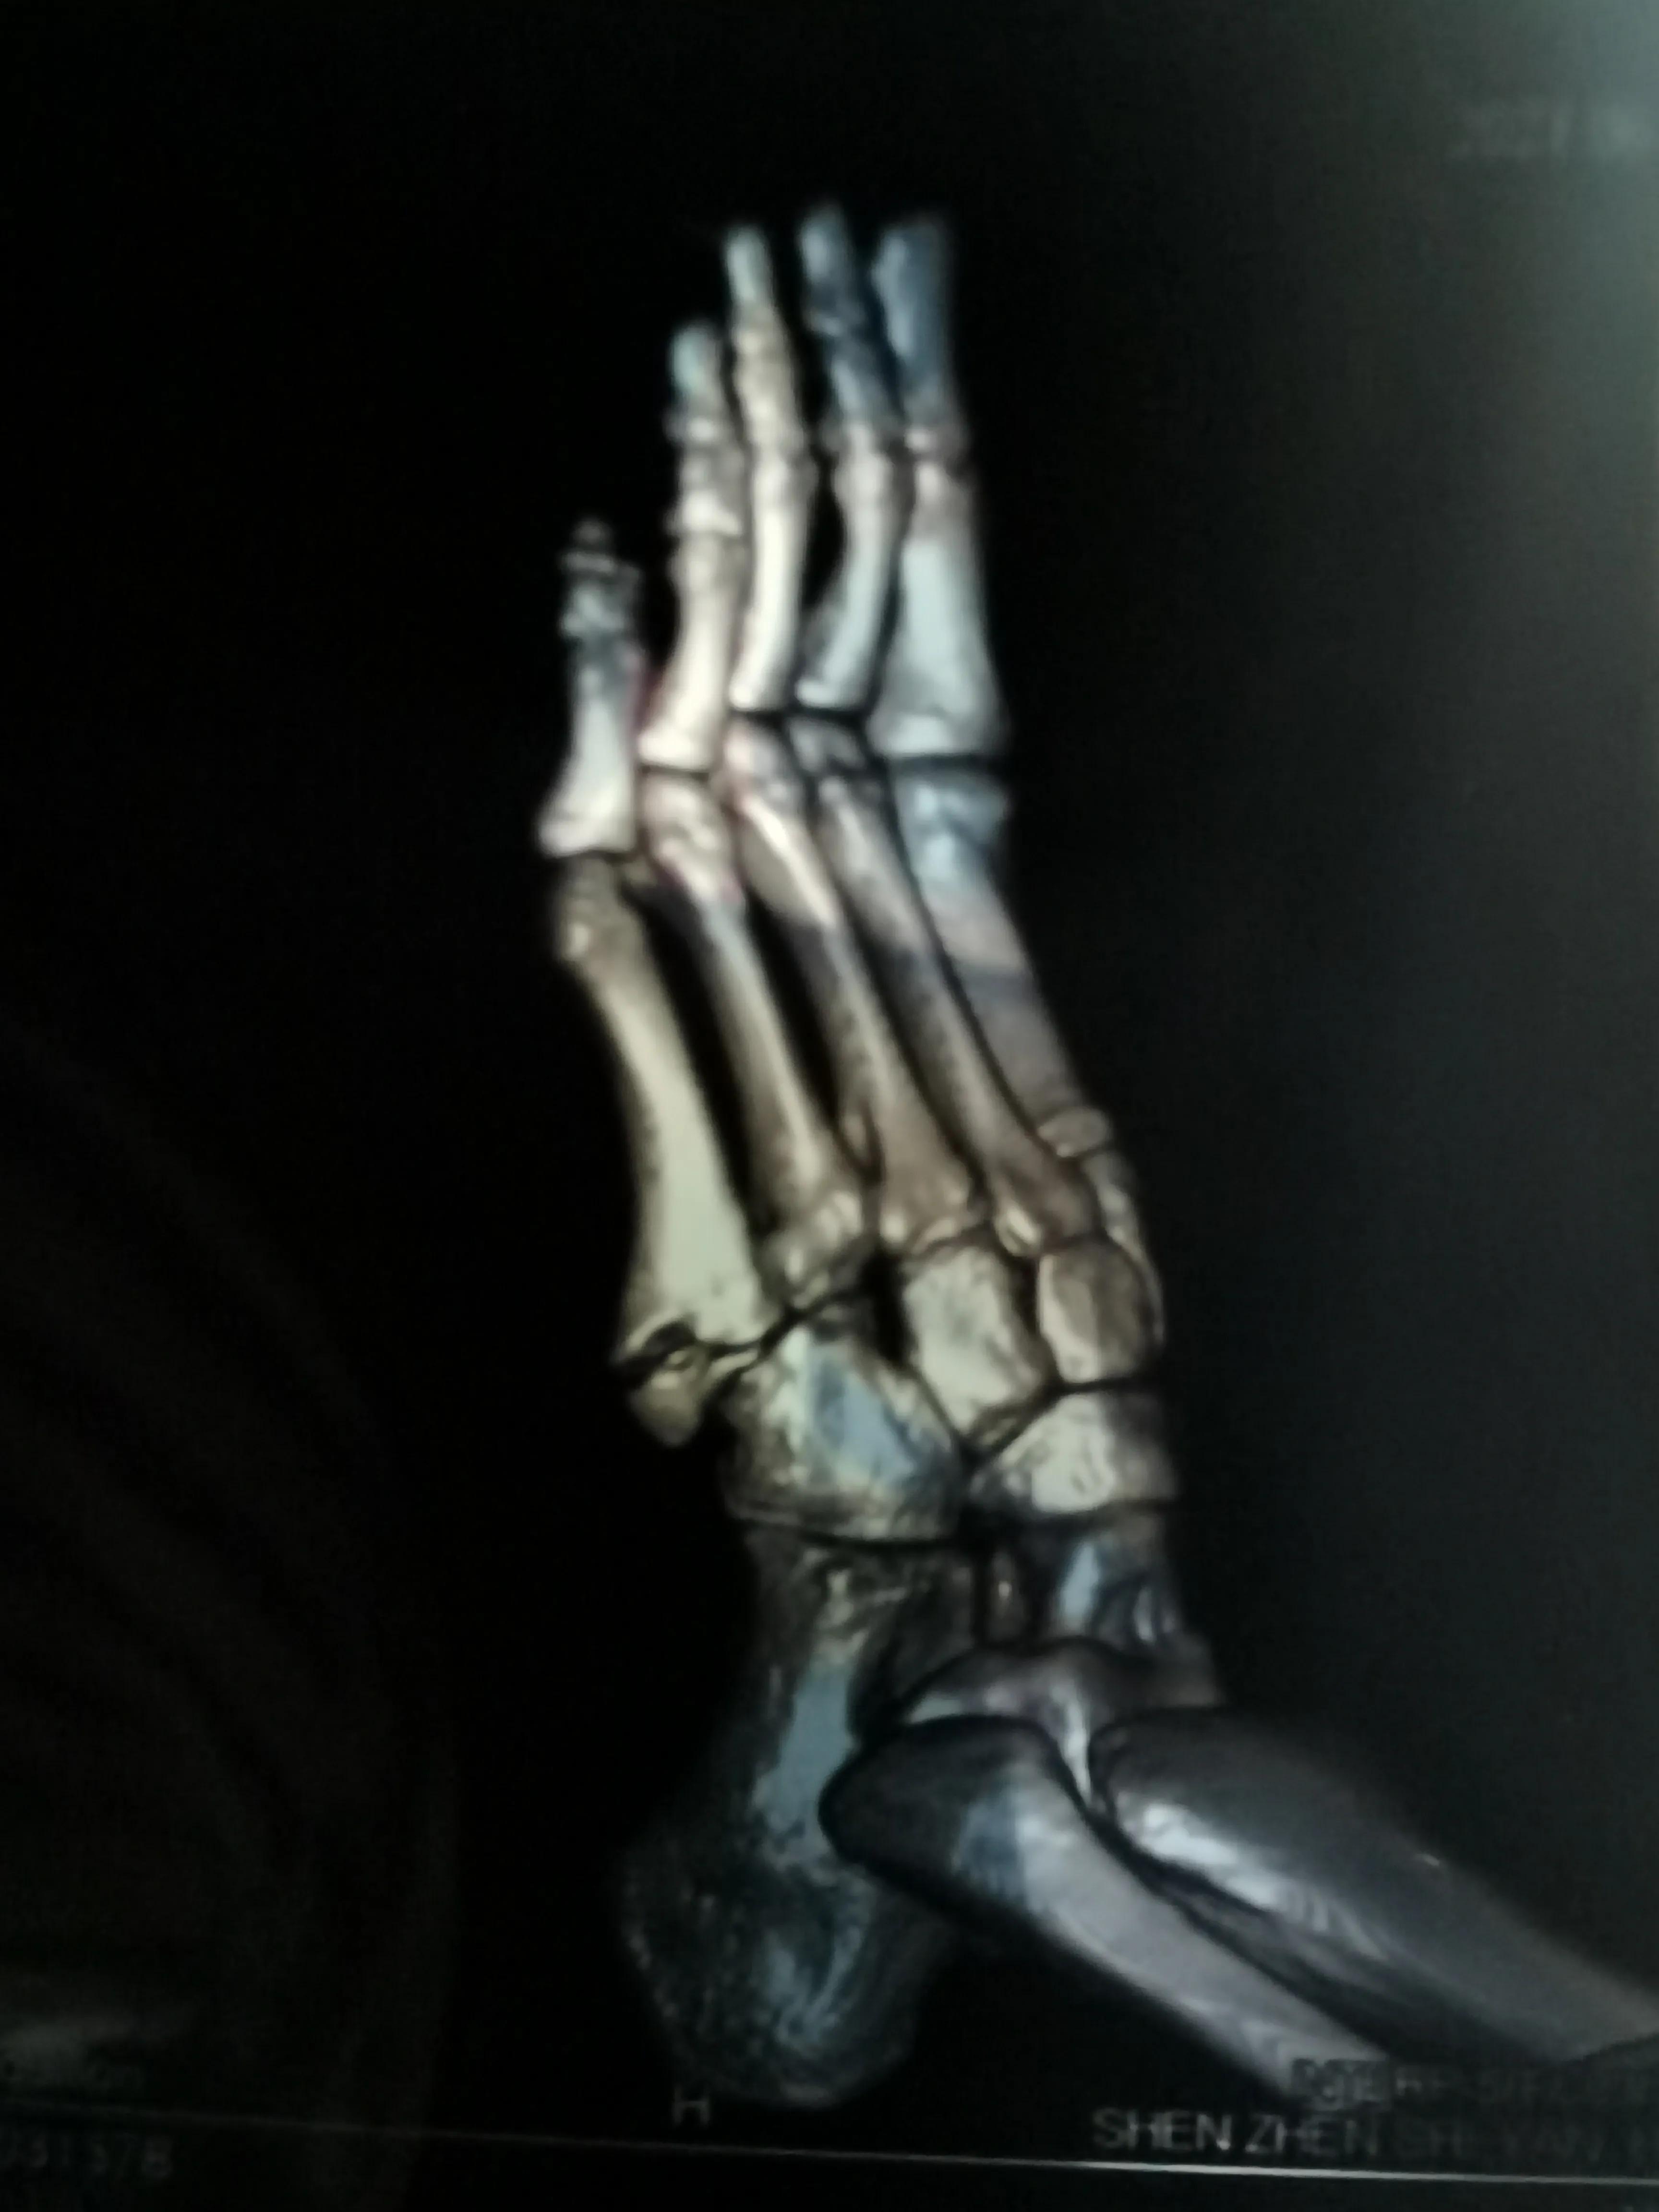

看片子骨缝比较大了,有点移位,而且中间崩碎了一块,一直找不到,后来复查才发现那个碎片掉落在骨缝当中了

此图可以看见中间碎片在骨缝里面

6月底复查,骨缝小的地方已经有了一点愈合的痕迹,医生说如果手术可以在红线位置打个钉子,但是现在打会破坏内部已经开始愈合的部分,建议继续保守……